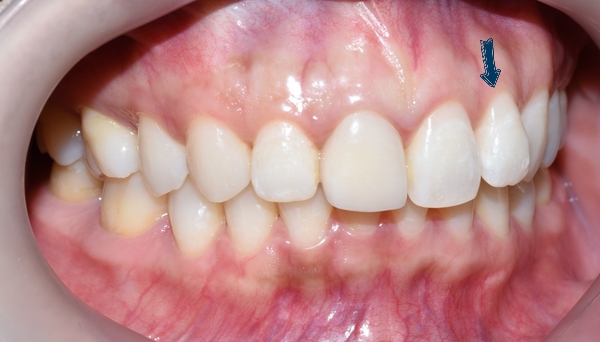

서울 시청역 연세예감치과 [사진공개 동의한 환자분 사진입니다.]

이번 소개해 드릴 분은 몇 년 전 다른 치과에서 교정을 하셨는데

다시 앞니가 튀어나와보인다는 것을 해결하기 위해 오신 환자분입니다.

많이 튀어나오진 않았지만, 유독 이런 이가 사진을 찍을 때 도드라지게 보이죠.

사진에서 한 치아가 옆 치아들과 비교해 유독 튀어나온 것 같은 느낌? 있으시죠?